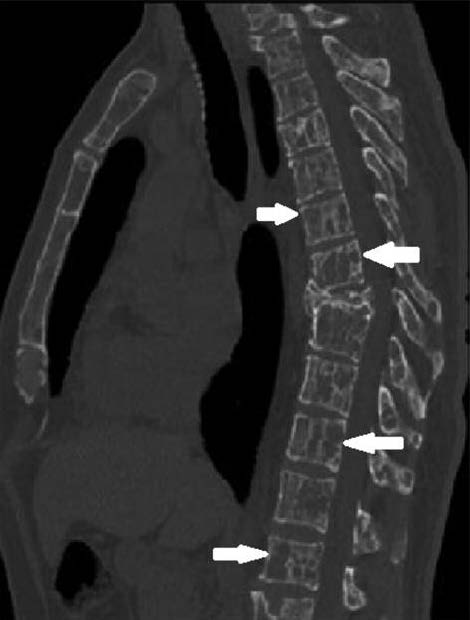

Пациент 45 лет. В возрасте 30 лет (в 2004 г.) появилась сильная боль в нижнегрудном отделе позвоночника. На компьютерной томографии (КТ) в 2006 г. визуализирован компрессионный перелом тела VIII грудного позвонка с формированием угловой кифотической деформации грудного отдела позвоночника до 151º, без значимой компрессии спинномозгового канала. В обеих полудужках VIII грудного позвонка определялись крупные очаги деструкции костной ткани, ограниченные подчеркнутым корковым слоем с фрагментарным его прерыванием, очаги деструкции заполнены содержимым пониженной мягкотканой плотности (до 27–28 HU) без распространения его за пределы костей. Помимо этого в костях зоны сканирования определялись немногочисленные разрозненные достаточно четко очерченные очаги деструкции костной ткани округлой и овальной формы размером от 2,5 до 15 мм, часть из них выходила на контур костей с прерыванием коркового слоя; в толще отдельных из очагов имелись костной плотности фрагменты точечного и линейного вида (рис. 1).

Рис. 1. Компьютерная томограмма грудного отдела позвоночника (2006 г.): компрессионный перелом тела Th8; немногочисленные очаги деструкции в костях.

По клиническому течению и рентгенологической картине поражение скелета при AL-A отличалось от ММ. В большинстве очагов деструкции видны костные фрагменты точечного и линейного вида (button sequestration). Отсутствовала динамика размеров частично обызвествленных мягкотканых образований в переднем отрезке II ребра справа и паравертебральных отделах VIII грудного позвонка, отмечалось спонтанное «рубцевание» участка деструкции в правом поперечном отростке и полудужке I грудного позвонка (в отсутствие какой-либо терапии). Следует также отметить достаточно низкую плотность содержимого очагов деструкции и отсутствие его экстраоссального распространения из больших зон деструкции. Подобные изменения нехарактерны для ММ и могут соответствовать нелангергансоклеточному гистиоцитозу (болезни Эрдхейма–Честера), однако данный диагноз исключен при многократных гистологических исследованиях биоптатов костей. Важно отметить, что амилоид накапливает радиоактивный изотоп на ПЭТ-КТ, т.е. проявляет себя как метаболически активная ткань.